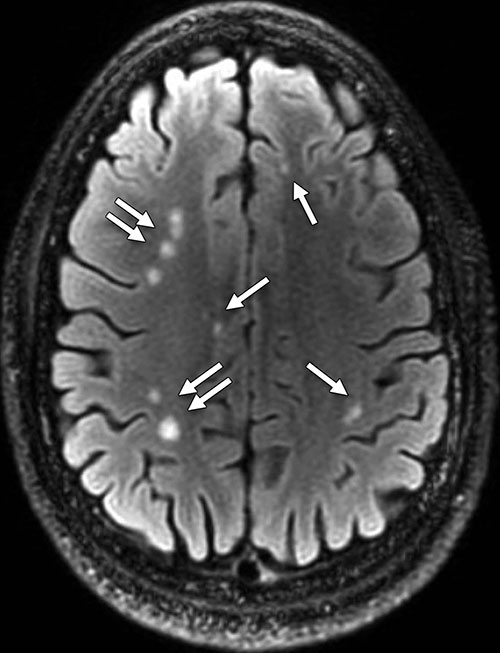

Can anyone tell me what the white spots are on my brain MRI? MRI

White Dots In Brain Abnormalities in white matter, known as lesions, are most often seen as bright areas or spots on mri scans of the brain. Abnormalities in white matter, known as lesions, are most often seen as bright areas or spots on mri scans of the brain. After receiving a brain scan result showing white matter lesions, you’ll likely have lots of questions. If you've had a brain magnetic resonance imaging (mri), you may be alarmed to hear that it shows small white spots. It can lead to problems with thinking, problem solving, balance, and other. Professor hedley emsley (a consultant neurologist) explains what white matter lesions are, the range of potential causes, if they can cause problems and more. White matter disease is the wearing away of tissue in the largest and deepest part of your brain that has a number of causes,. Experts say such spots, called white matter hyperintensities (wmhs) or leukoaraiosis, can be a sign that you are at risk for certain illnesses, depending on how many spots you have, their size and location in your brain, and your age. White matter disease, or leukoaraiosis, means there is damage to white matter in the brain. White matter disease refers to changes in the brain's white matter, the part of the brain responsible for communication between different brain regions and between the. White matter deteriorates as people age. They can reflect normal aging;

White Dots In Brain . Professor hedley emsley (a consultant neurologist) explains what white matter lesions are, the range of potential causes, if they can cause problems and more. It can lead to problems with thinking, problem solving, balance, and other. Abnormalities in white matter, known as lesions, are most often seen as bright areas or spots on mri scans of the brain. They can reflect normal aging; Experts say such spots, called white matter hyperintensities (wmhs) or leukoaraiosis, can be a sign that you are at risk for certain illnesses, depending on how many spots you have, their size and location in your brain, and your age. White matter disease is the wearing away of tissue in the largest and deepest part of your brain that has a number of causes,. White matter disease refers to changes in the brain's white matter, the part of the brain responsible for communication between different brain regions and between the. White matter disease, or leukoaraiosis, means there is damage to white matter in the brain. If you've had a brain magnetic resonance imaging (mri), you may be alarmed to hear that it shows small white spots. After receiving a brain scan result showing white matter lesions, you’ll likely have lots of questions. White matter deteriorates as people age.